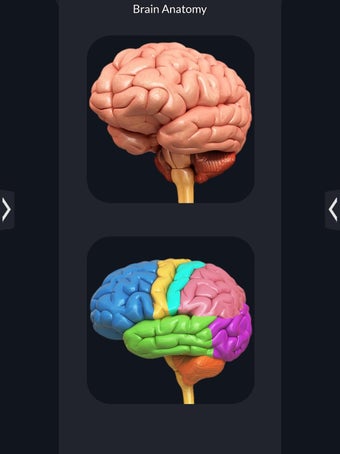

برنامج تشريح الدماغ Pro هو تطبيق تعليمي لدراسة تشريح الدماغ البشري. تم تصميم هذا التطبيق لكل من الطلاب الطبيين والجمهور العام. يتيح للمستخدمين استكشاف الدماغ من جميع الزوايا وعرض التشريح بطرق مختلفة. إنه أداة سهلة الاستخدام تتيح للمستخدمين تدوير 360 درجة والتكبير والتصغير وتحريك الكاميرا حول نموذج ثلاثي الأبعاد واقعي للغاية. يتيح للمستخدمين القدرة على تحديد الأجزاء وعرضها بالأشعة السينية وإخفائها وإظهارها وعرض الرسوم المتحركة في الوقت الحقيقي والرسم أو الكتابة على الشاشة ومشاركة لقطات الشاشة ونطق الصوت لجميع مصطلحات التشريح والمزيد. إنه تطبيق تعليمي مجاني.